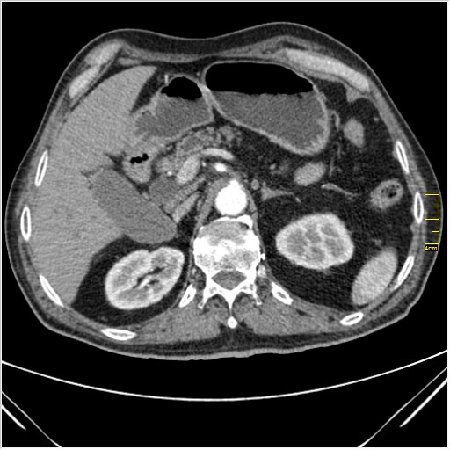

Мужчина 62 года с желтухой

Опухоль головки поджелудочной железы, расширение холедоха и панкреат. протока (Double Channel sign)

Карциномы панкреас гиподенсны на КТ с болюсом, т.к. содержать много соединительной и фиброзной ткани, в отличие от нормальной ткани железы, которая (как любая железа) хорошо васкуляризирована. Поэтому если видим в панкреас солидное гиподенсное образование - всегда настораживает на предмет рака. Второй момент: обязательная оценка взаимоотношения опухоли к ВБА и ВБВ, на предмет оценки операбельности.